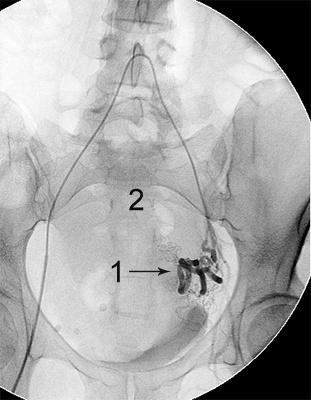

Ангіограми до та після емболізації:

міома матки до емболізації    міома матки після емболізації

Розширена звивиста ліва маткова артерія (1),

вузол лейоміоми матки (2)

Після емболізації частками: маткова артерія

збережена (1), лейоміома не контрастується (2).